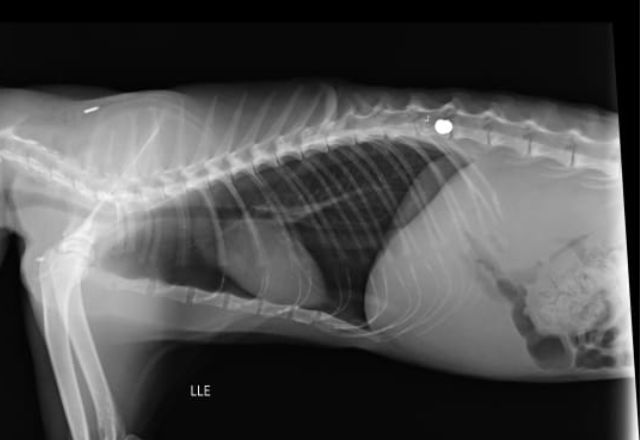

O gato chegou à clínica com anemia e precisaria passar por uma cirurgia bastante delicada para tentar reverter os danos causados pelo projétil, que atingiu a coluna. No entanto, seu estado de saúde se agravou nos últimos dias e ele acabou não resistindo.